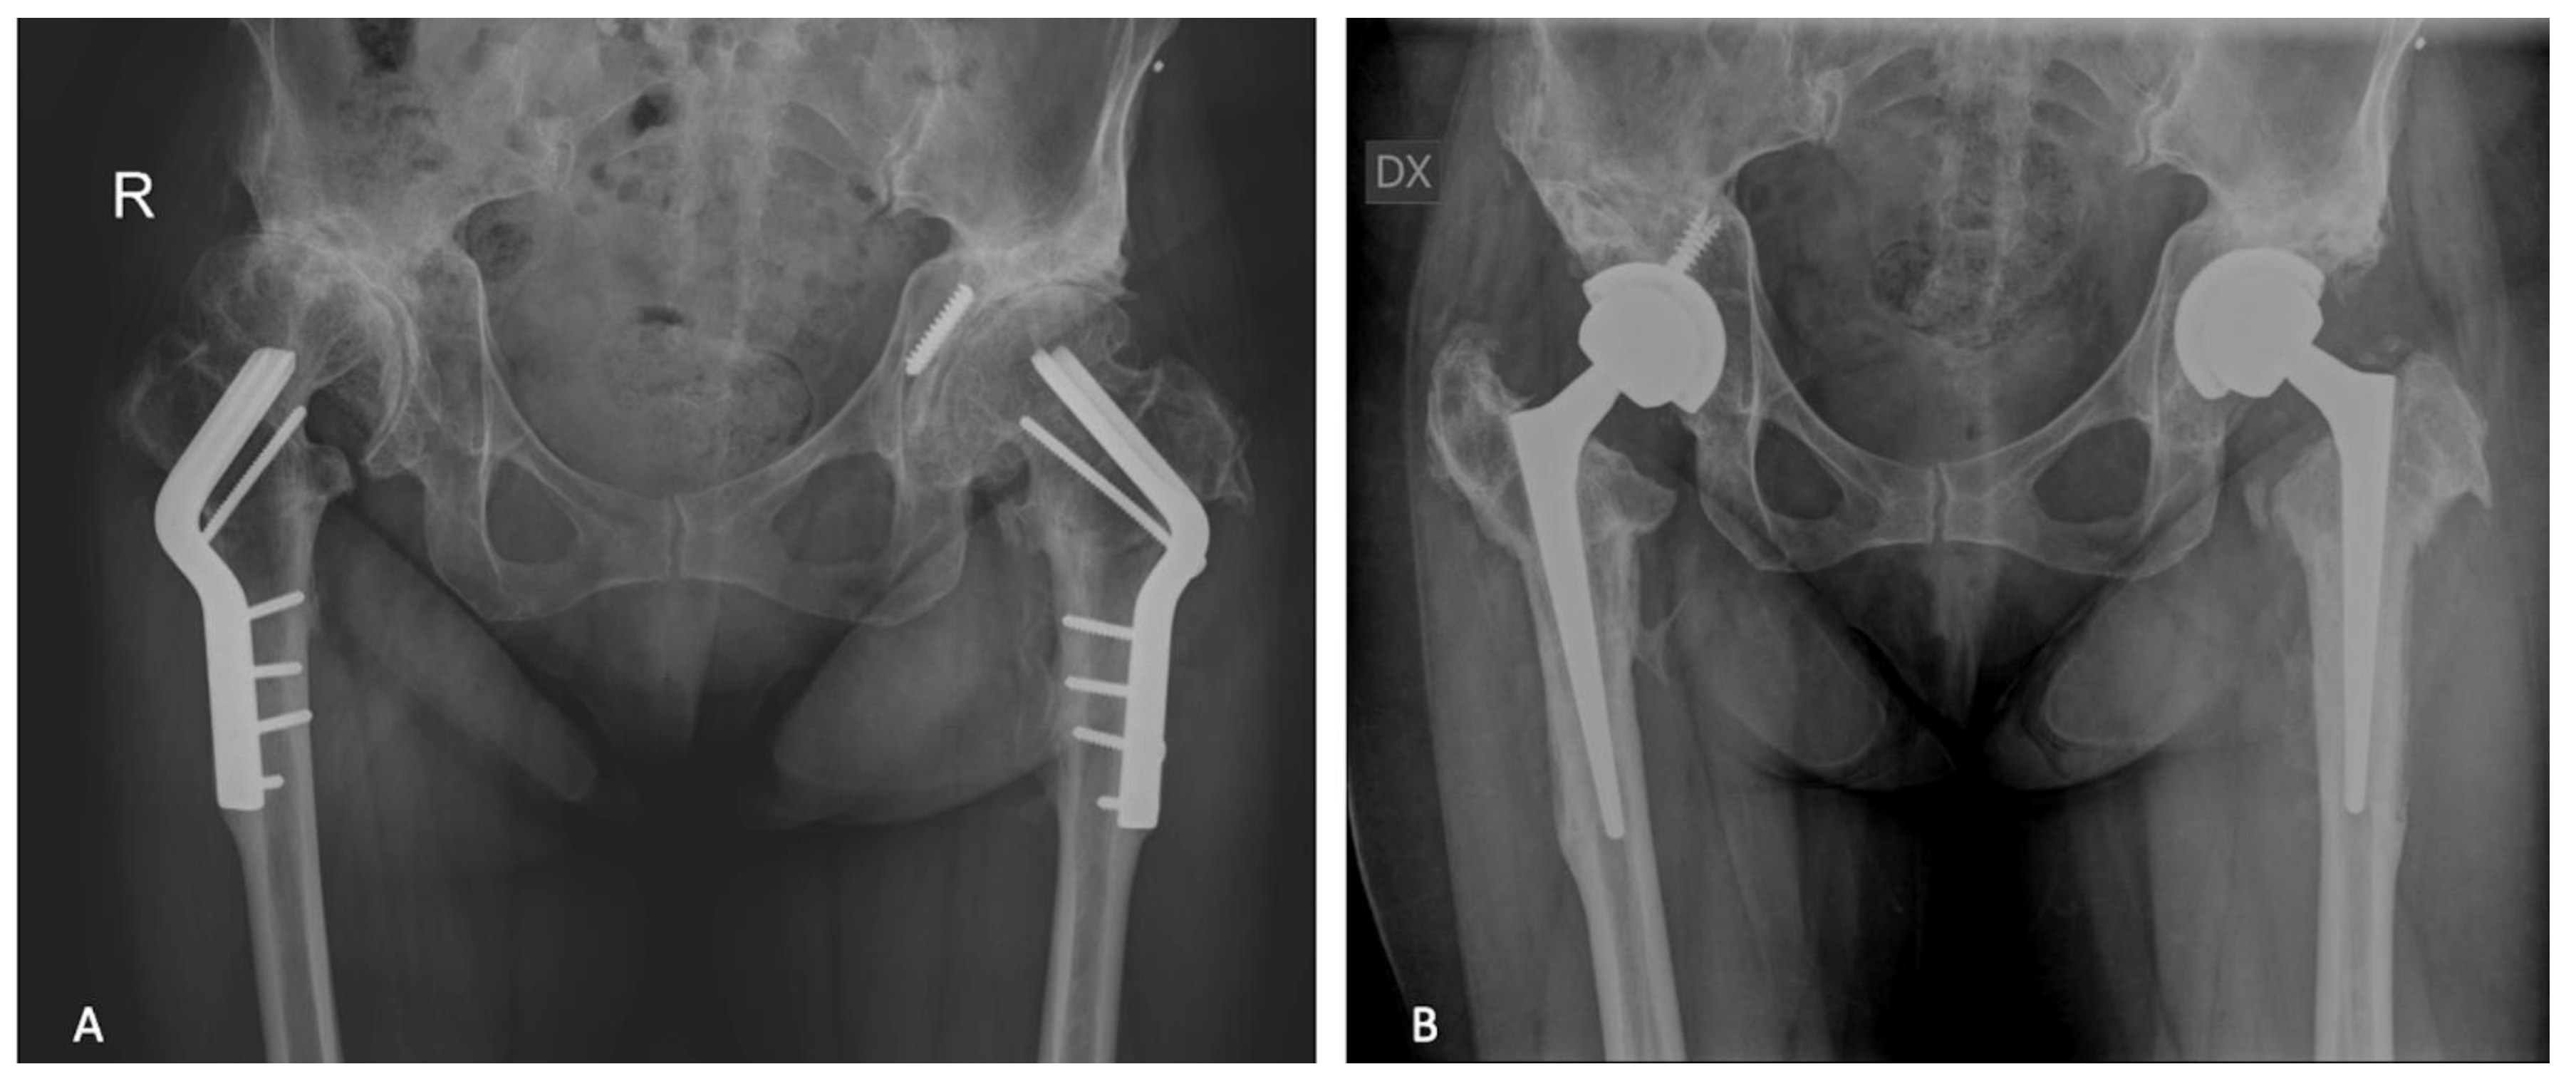

| Post-Traumatic Group | Post-Preventive Group | |

| Number of hips | 87 | 40 |

| Hip dysplasia | - | 23 (57%) |

| Epiphysiolysis | - | 14 (35%) |

| Osteonecrosis | - | 1 (2%) |

| Arthrodesis | - | 2 (5%) |

| Hardware removed | ||

| Screws | 35 (27%) | 13 (10%) |

| plate and screws | 6 (5%) | 9 (7%) |

| Angled blade plate | - | 12 (10%) |

| Tantalum rod | - | 1 (1%) |

| K wires | - | 1 (1%) |

| Camber | - | 4 (3%) |

| Type of femoral stem used for conversion THA | ||

| Cementless | ||

| Conventional tapered | 31 (24%) | 7 (6%) |

| Short tapered | 16 (13%) | 8 (6%) |

| Conical | 4 (3%) | 21 (17%) |

| Long revision | 31 (24%) | 4 (3%) |

| Resurfacing | 1 (1%) | - |

| Cemented | ||

| Conventional tapered | 4 (3%) | - |